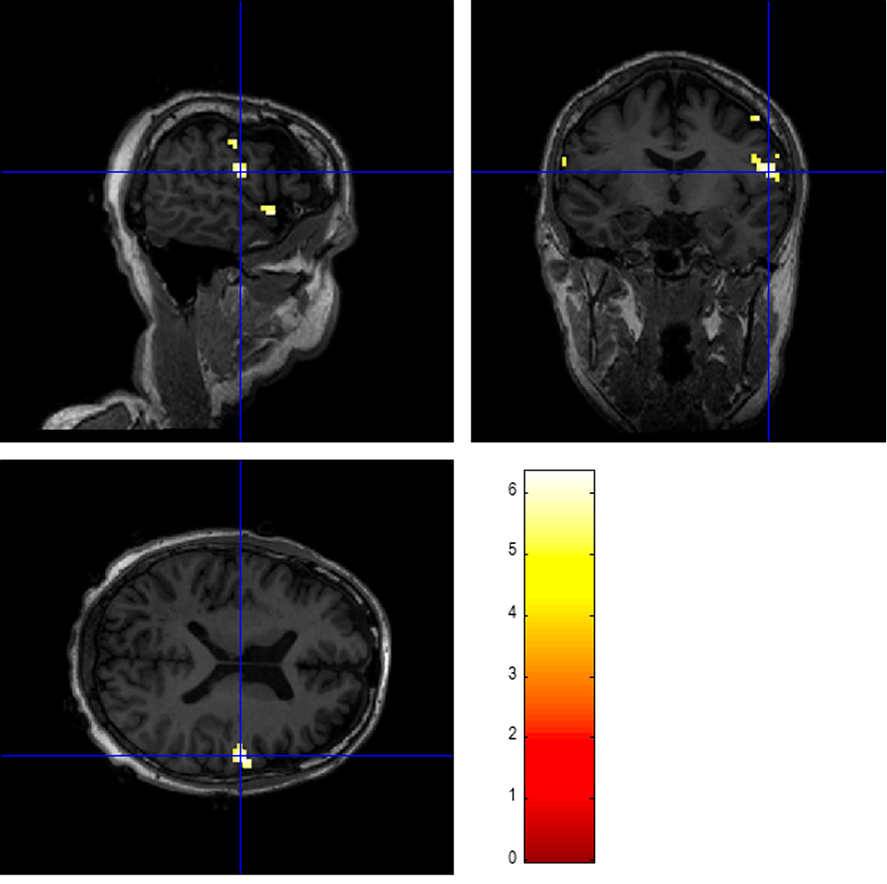

At CNSLab, research based on simultaneous EEG-fMRI measurements is conducted to identify potential epileptogenic foci in patients with epilepsy. Below are example results obtained from one patient. Simultaneous EEG-fMRI recording was performed, during which 26 interictal epileptiform discharges (IEDs) were registered across three 10-minute sessions. Based on the occurrence times and durations of IEDs, a regressor was created for statistical analysis of the fMRI functional data using the GLM model. The analysis performed in SPM12 software enabled the identification of the activation area with the highest statistical strength (highest T value), which may be associated with interictal discharges. The main 4 regions with the highest T-score value were located in the following anatomical structures: postcentral gyrus, planum polare, precentral gyrus, middle temporal gyrus.

Results of the SPM Analysis of Functional fMRI Data for a Selected Patient, FWE correction, p<0.05. The color scale reflects the T-score values. The result was superimposed on an anatomical T1w image and presented in a slice showing the maximum T value.